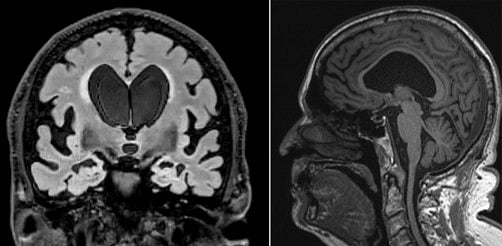

Two MRI scans for Dick Nash show some of the classic signs of NPH. The scan on the left taken from the front shows large ventricles, disproportionately enlarged subarachnoid spaces at the Sylvian fissures, and narrowing of the sulci at the vertex. Newswise

Based on his scans, the ventricles in the middle of Dick’s brain had enlarged a significant amount, likely caused by excess CSF and reduced outflow, which can disrupt communication between the brain and legs.

There also was evidence of disproportionately enlarged grooves in the brain, which happens when CSF is trapped in those spaces. On scans, this can look like brain shrinkage, which may have contributed to Dick’s earlier misdiagnosis.